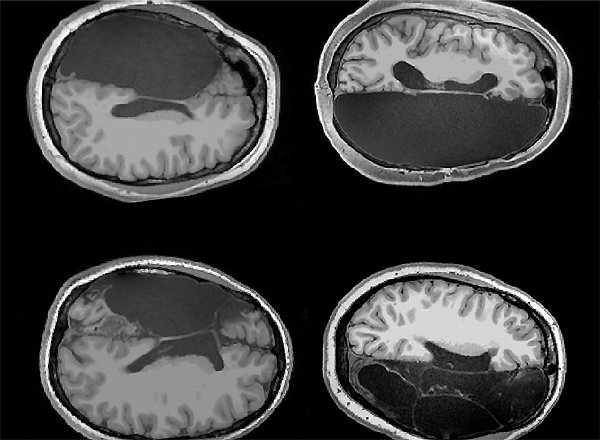

12.12.2019 | Нейропсихология

В экстремальных случаях эпилепсии, когда судороги пациента неустранимы и не реагируют на другие виды лечения, врачи могут выполнить редкую нейрохирургическую процедуру, называемую гемисферэктомией — удаление половины мозга. Звучит ужасно, однако, как ни удивительно, люди вполне восстанавливаются... »»»